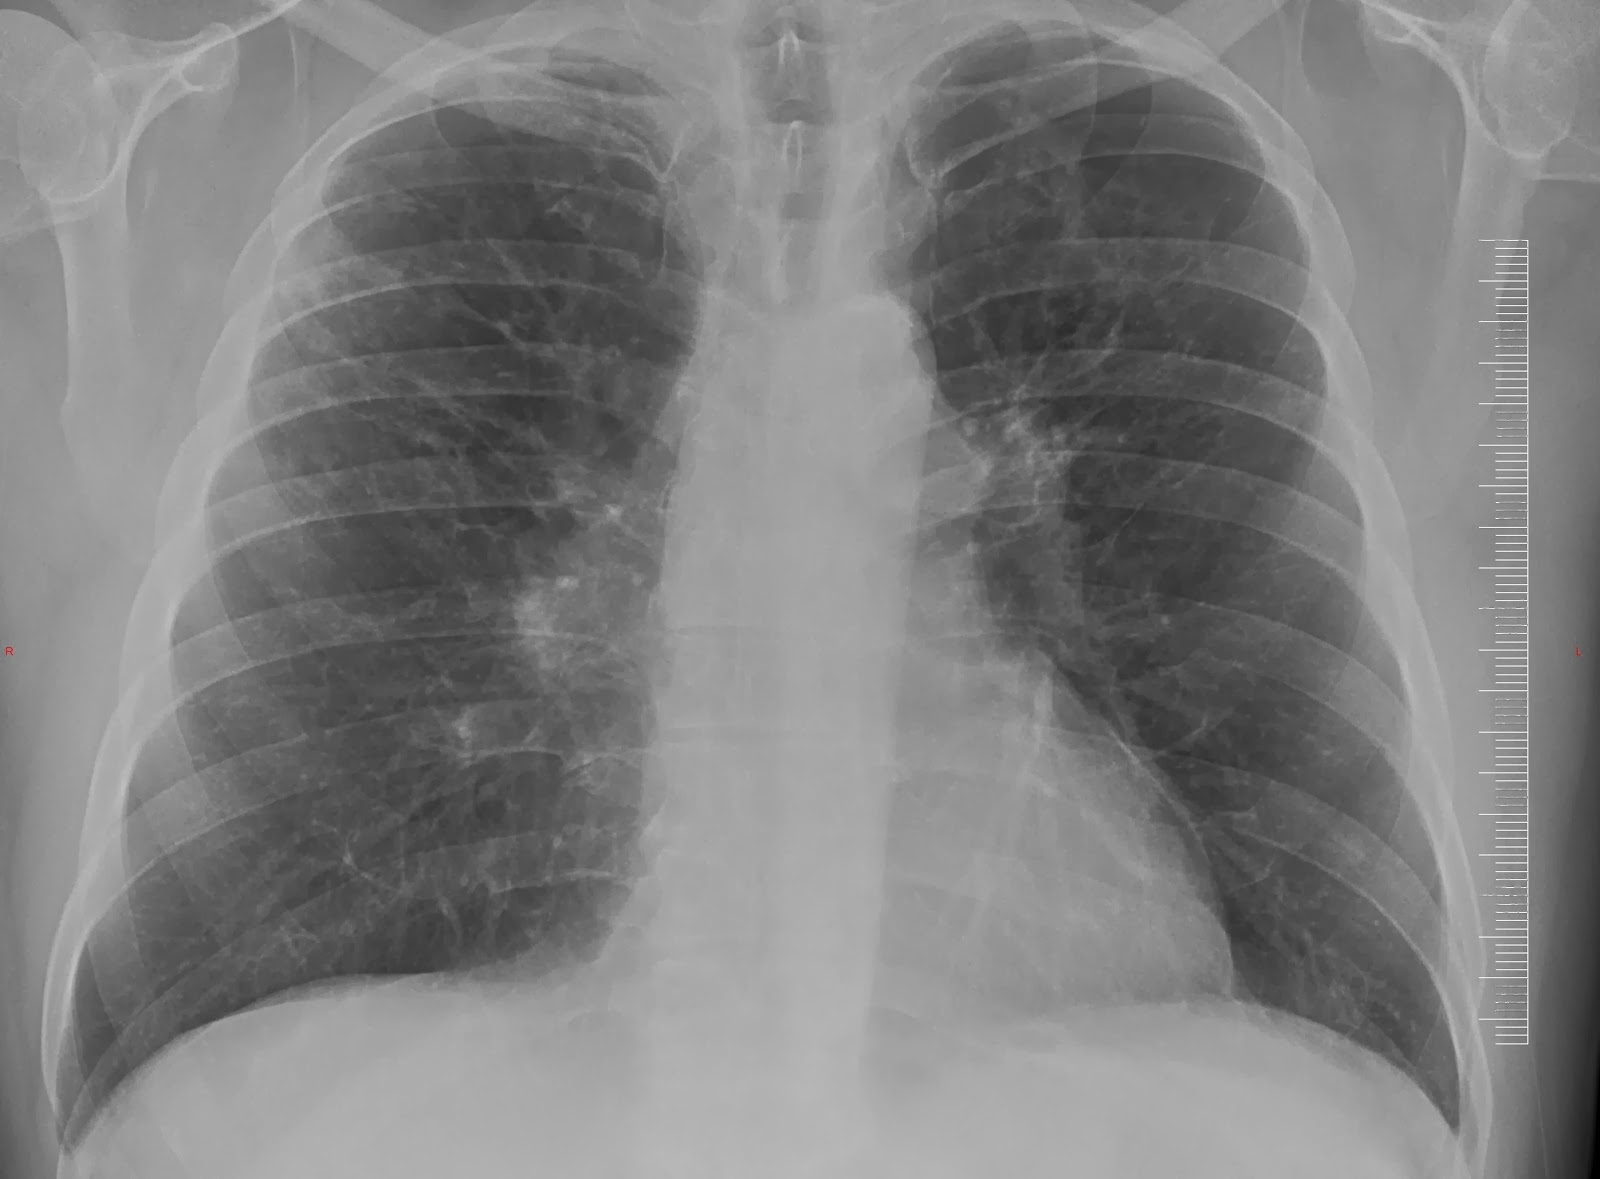

- In comparing the new chest X ray to the prior years X ray, the doctor displayed an overlay of the new and the old. It was clearly evident that more scar tissue had formed on the lungs in the twelve months since my last visit. The CBD was clearly progressing. (See pictures below -- more cloudiness is evident)

| September 2012 |

| September 2013 |